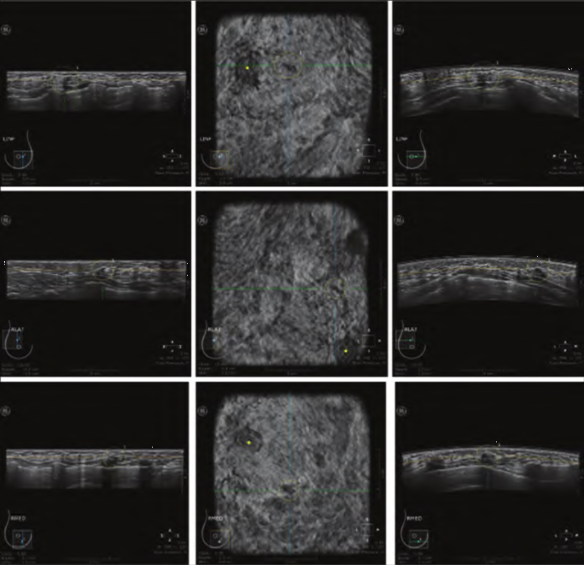

a. ABUS数据及乳腺癌区域(黄色标注); b. 深度学习辅助检测模型生成的乳腺癌概率图;c.3D显示的乳腺癌标注(红色)及辅助检测结果(灰色);d. ABUS图像上显示的自动检测结果(绿色)。

深圳大学团队基于ABUS影像开发的辅助检测系统结果